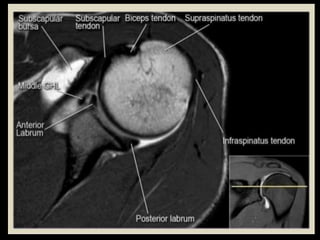

Hip Joint.

Shoulder

Joint.